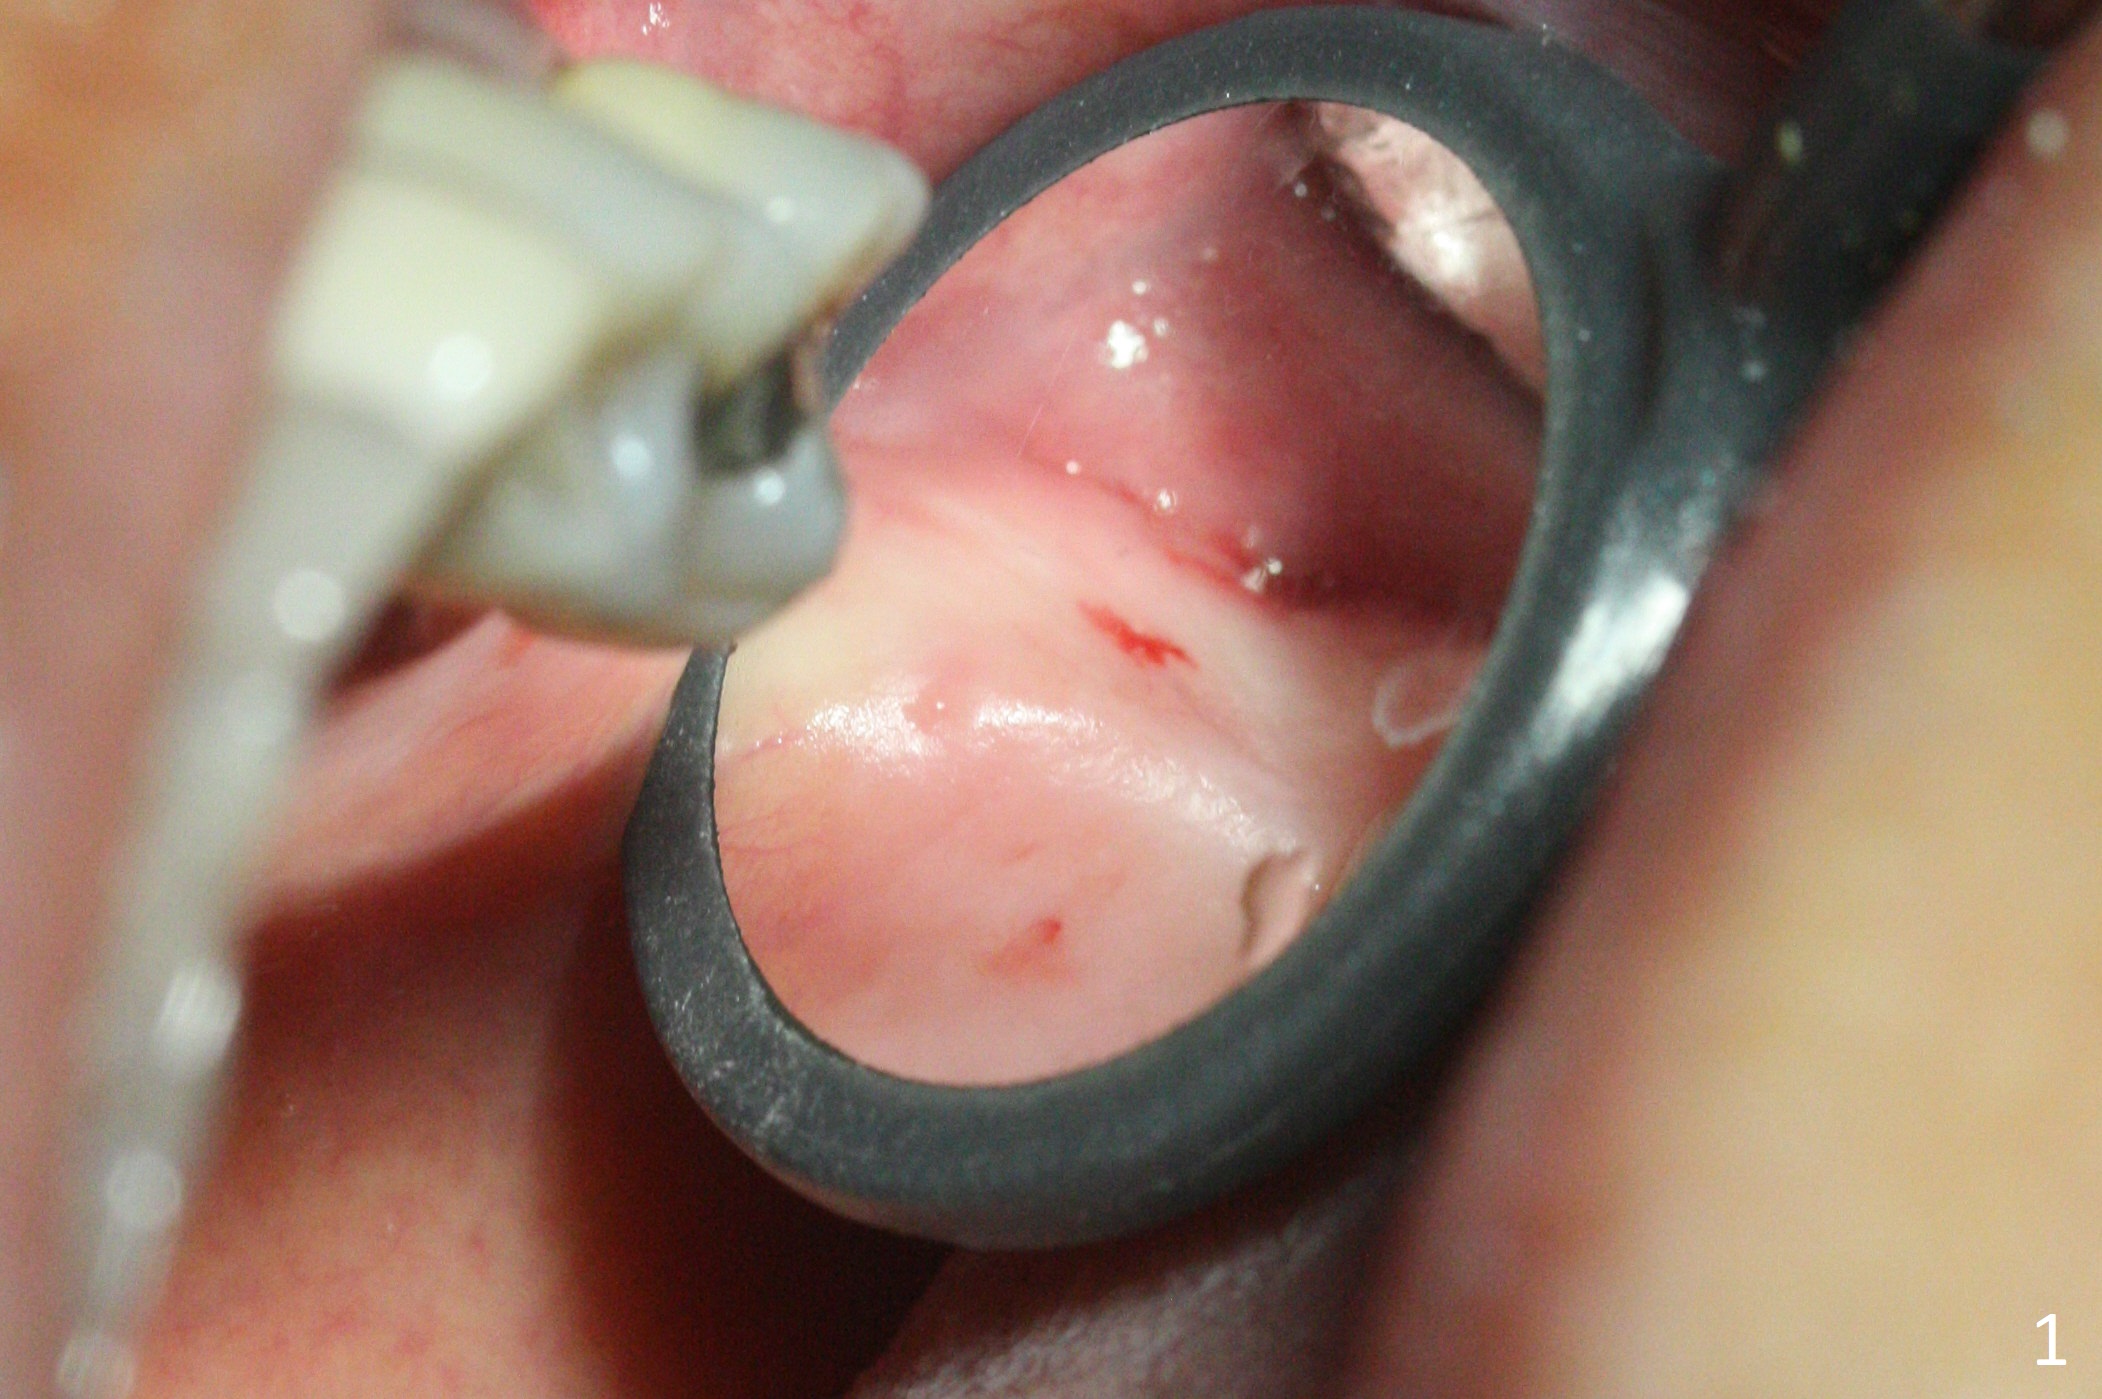

The ridge is pointed at the site of #15 (Fig.1). A 1.2 mm initial drill is used to start osteotomy for 10 mm, followed by an incision over the ridge mesiodistally for ~ 8 mm. After tapping the #15 C blade, the 1st Bone Expander 1.0/1.6 mm) is inserted for ~ 11 mm (Fig.2, 20 Ncm). Bone expansion continues until #4 Expander (2.4/3.7 mm, Fig.3). When 4x11 mm and 4.5x11 mm dummy implants are placed (Fig.4), insertion torque remains 20 Ncm. Following placing allograft with 3-4 amalgam carriers, a 5x11 mm IBS implant is placed with 20 Ncm (Fig.5,6). In fact the implant turns when an abutment is placed. When the implant is re-inserted, torque decreases to 10 Ncm. Instead a healing screw is placed. The low torque value is due to soft bone and failure to underprep. #4 Expander (Fig.3) seems larger than 4.5 mm implant (Fig.4). #3 Expander (1.7/3.1 mm) should have been used prior to definitive implant placement. The implant appears to have osteointegrated 3 months postop (Fig.7); impression is taken. The bone density at the crest increases 1.5 years post cementation (Fig.8 *, as compared to Fig.6), although there is mild bone loss. Implant placement should be deep when bone expansion is carried out. The tooth #14 develops a buccal fistula, corresponding to periapical radiolucency of the mesiobuccal root (Fig.9 white >). The abutment of #15 may be incompletely seated (black <). PA taken when RCT of #14 is finished does not show the incomplete seating of the abutment (Fig.10). Since there appears no history of abutment screw loosening, the abutment is not reseated when #14 is prepared for crown. Recall 3 years 7 months post cementation shows incomplete seating of the abutment (Fig.11 >). After crown proximal reduction (Fig.12 *) and clockwise turn of the crown, the abutment appears to be completely seated. When the case returns from lab, the separate crown and abutment cannot be connected to the fixture because of soft tissue adaptation and change in a month. The abutment is reseated to the fixture analog in the model and the crown is recemented with temp bond (in case of misalignment) while making sure that the crown has the best proximal contact with the neighboring crown. With the abutment and crown in a unit, it is much easier to reseat the abutment with normal proximal contact. The torque is 20 Ncm. The access hole is closed with Cavit.